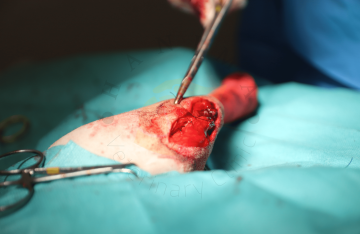

Amputace

Biopsie kosti